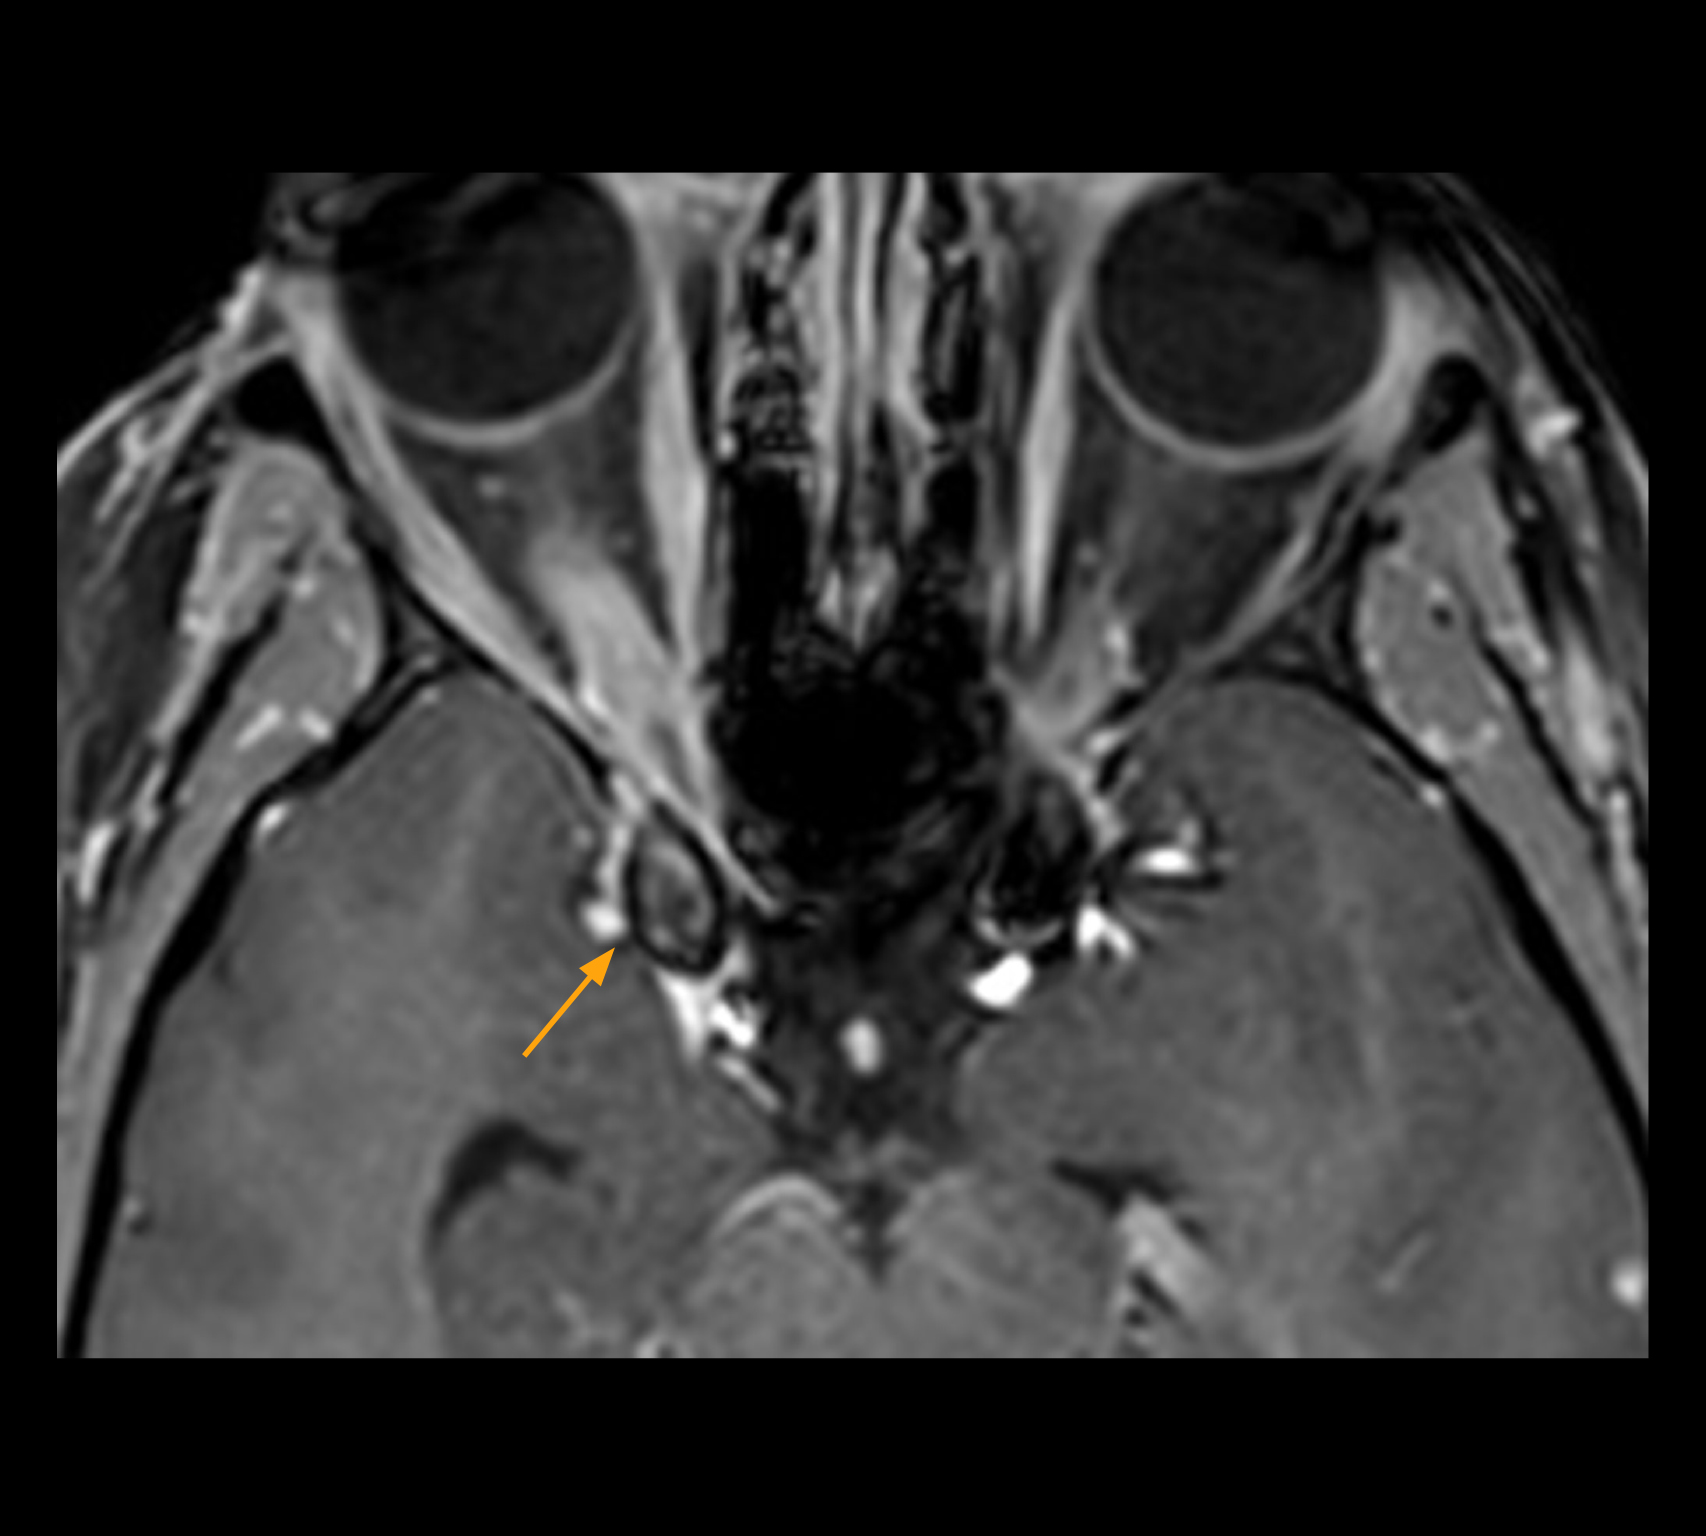

In select cases, the MR 7700 has helped the hospital’s physicians more clearly visualize pathology. “We’re definitely getting the impression that tumors are better delineated with the MR7700,” Dr. Heindel says. “For example, I examined a patient who had been diagnosed in another hospital with possible neuritis of the optic nerve. However, the MR 7700 images allowed me to diagnose it as an optic nerve sheath meningioma, a rare and often misdiagnosed, slowly growing tumor that wascausing the visual disturbances in the patient. The lesion was so well delineated on the high resolution MR 7700 images that our neurosurgeon decided he did not need a biopsy before proceeding directly with decompression of the optic canal and peeling away those tumor cells.”

High-resolution MRI impressively demonstrates the compression and narrowing of the right optic nerve in this case of optic nerve sheath meningioma (ONSM). The coronal T2-weighted images show the hyper-intense, half-moon shaped lesion, that is clearly visible in the axial T1W image after contrast injection (right). These imaging findings were so convincing that there sponsible neurosurgeon did not consider a pretherapeutic histological clarification.